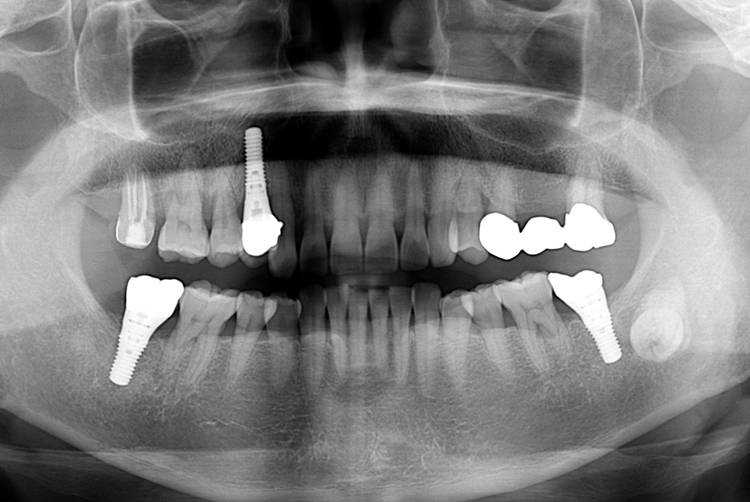

치료사례

세종치과의 진심 어린 치료는 결과로 말합니다.

실제 내원하신 환자분들의 치료 전·후 사례를 확인해보세요.

모든 치료사례 전후사진은 환자분의 동의하에 촬영되었습니다.

모든사진은 동일 환자분의 전후모습을 촬영하였으며, 사진의 밝기조절 외에 임의 수정이 없음을 알려드립니다.